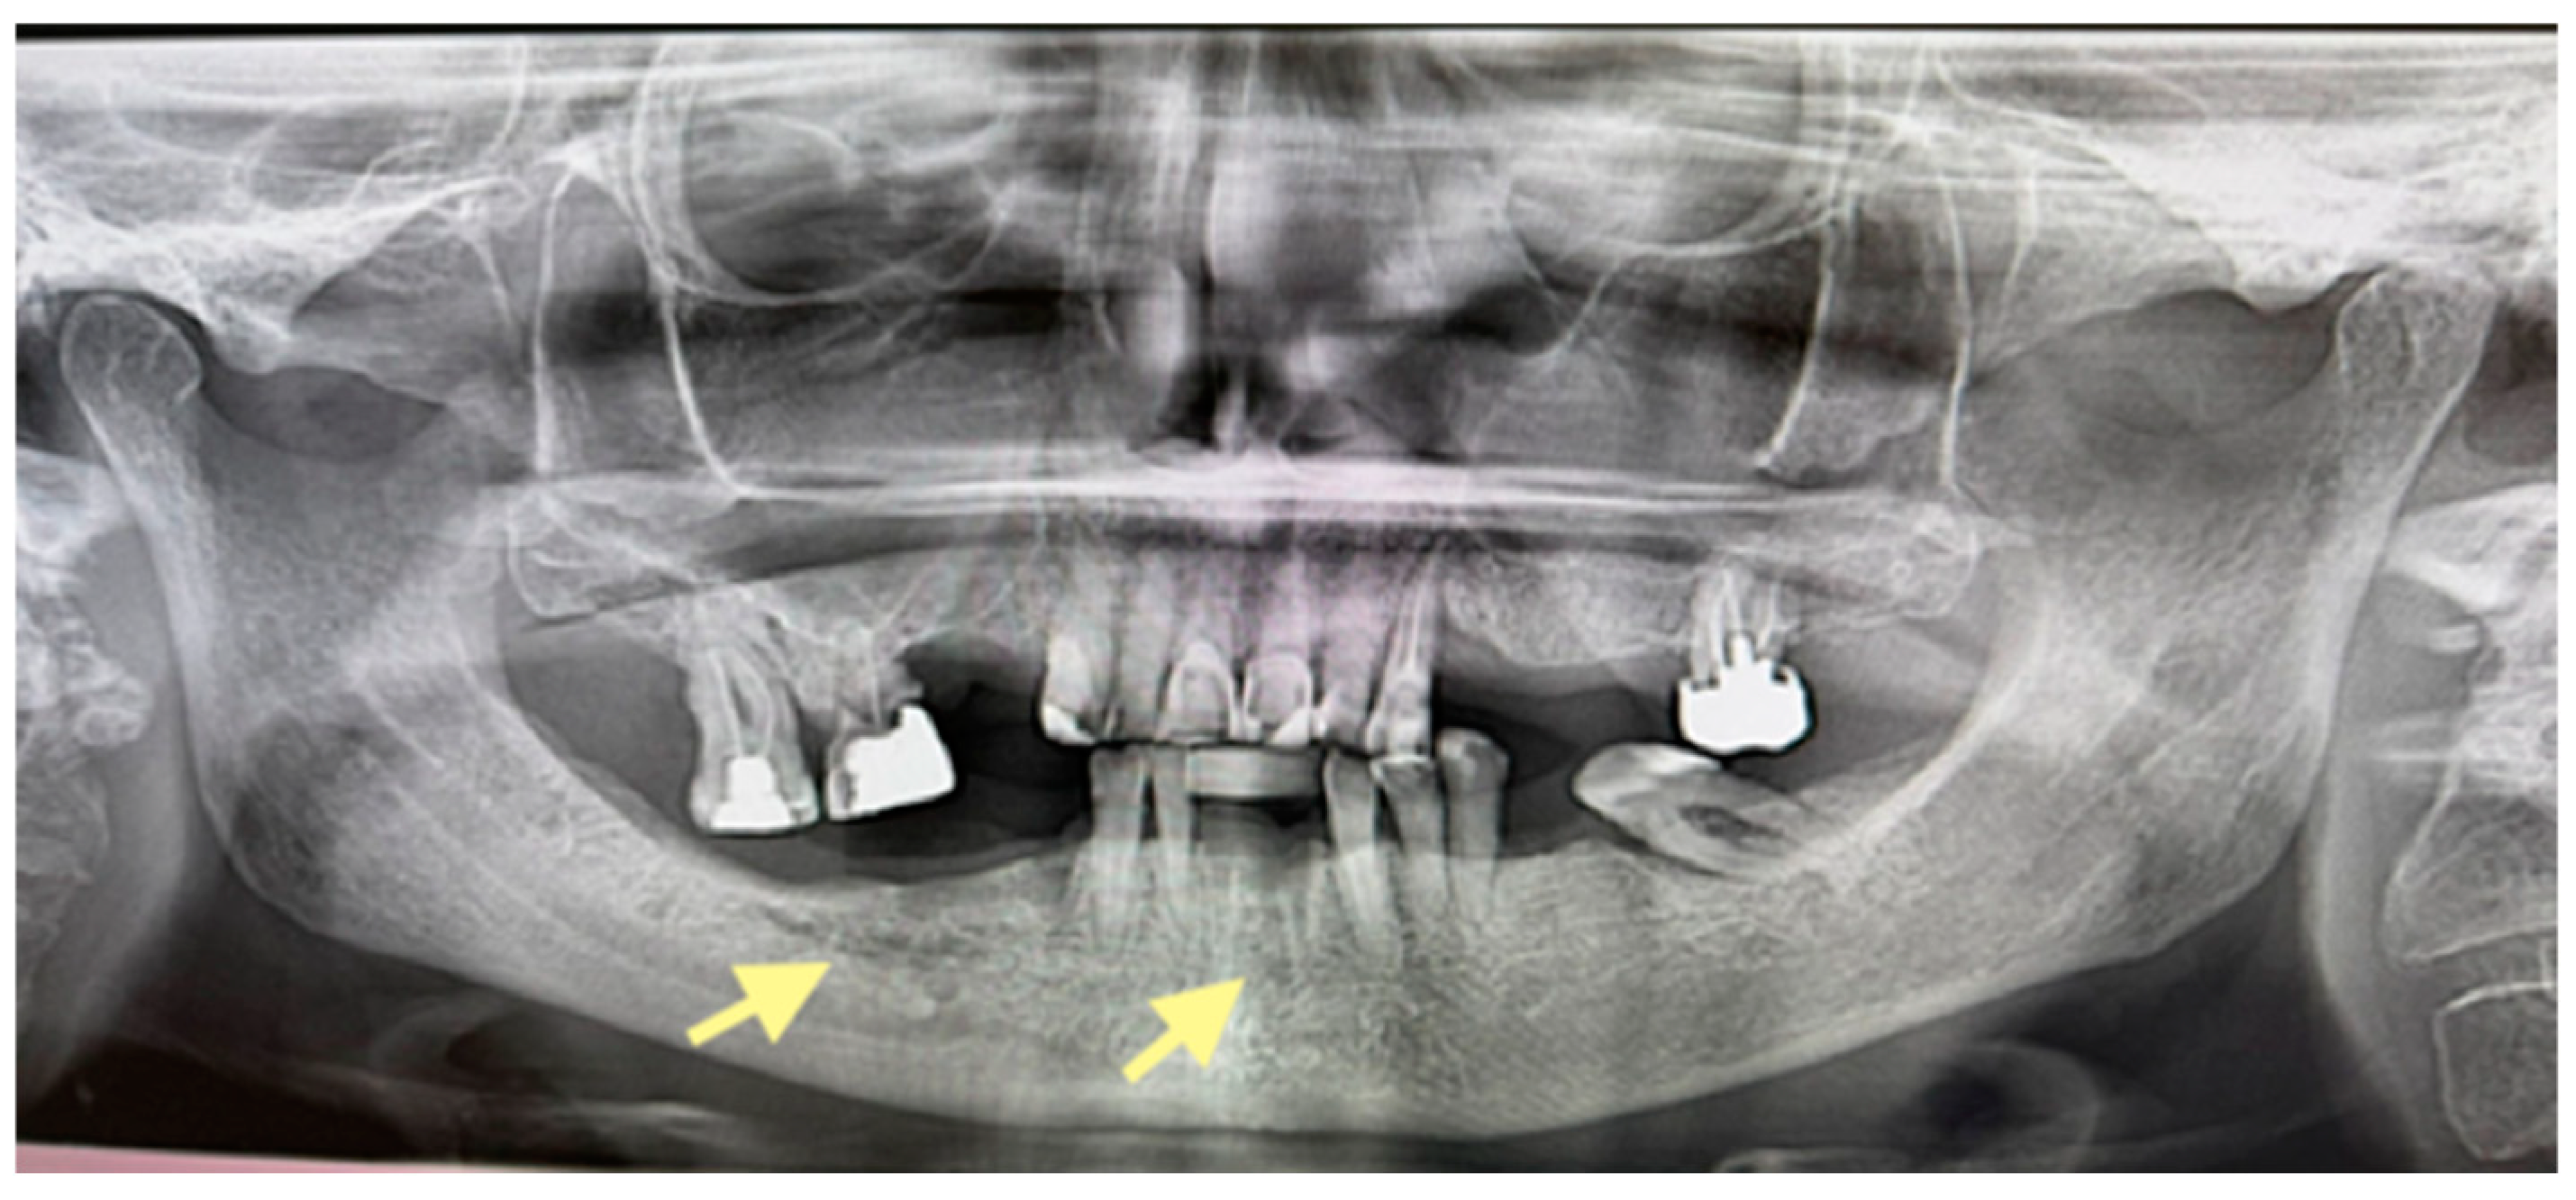

The second patient was an 82-year-old female with osteonecrosis of the mandible in the fourth quadrant, which developed after the removal of tooth 46 on November 2023 (see Figure 4). The patient had second-stage osteonecrosis of the jaw. Initially, the patient underwent a revision of the socket of the extracted tooth and was prescribed antibacterial therapy. Despite this treatment, the patient continued to complain of a non-healing wound on the lower jaw in the area of the molars with periodic purulent discharge. In addition, these complaints were supplemented by a complaint of an intraoral fistula on the lower jaw in the area of the frontal teeth. Therefore, in May 2024, the patient underwent surgery (sequestrectomy and application of A-PRF). After the operation, the patient’s condition improved, purulent discharge from the wound stopped, the pain ceased, and the postoperative wound closed completely (see Figure 4). However, after a month, dehiscence of the wound was noted. Therefore, it was decided to repeat the operation, performed on 4 April 2025, and, in addition, to expand the scope of the surgical procedure, the sequestrectomy of the lower jaw was performed not only in the region of dd45-46 but also in the central area, simultaneously applying A-PRF. As a result of the treatment, the surgical wound on the lower jaw in the area of the molars on the right healed completely, but in the area of the incisors, it closed partially (see Figure 5 and Figure 6).

Figure 4.

OPG (orthopantomogram) before surgery (12 January 2024). In the fourth quadrant, we do not see any changes, which are typical in the initial stages of osteonecrosis.

Figure 5.

OPG (orthopantomogram) performed on 21.08.2024.